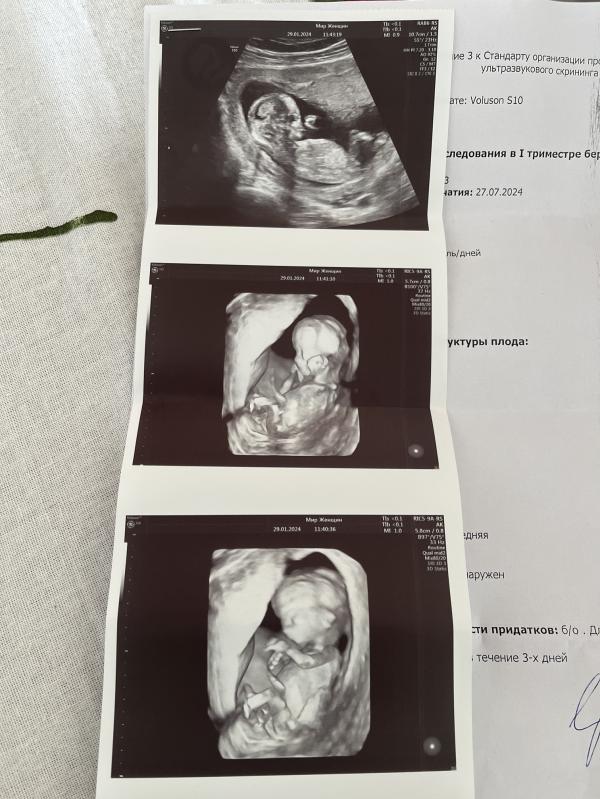

Мне тоже интересно кого видите на фото? Узист сказала что пока не видно.

На этих снимках не видно полового бугорка ) поэтому даже предположить невозможно

Видно же на первом снимке,